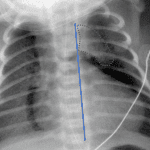

- Lucency outlining the mediastinum and uplifting and laterally displacing the thymus

- Pneumomediastinum (spinnaker sail sign)

Lucency outlining the mediastinum and uplifting and laterally displacing the thymus (spinnaker sail sign) consistent with pneumomediastinum.

Diffuse groundglass opacification of both lungs consistent with the patient’s diagnosis of transient tachypnea of the newborn.